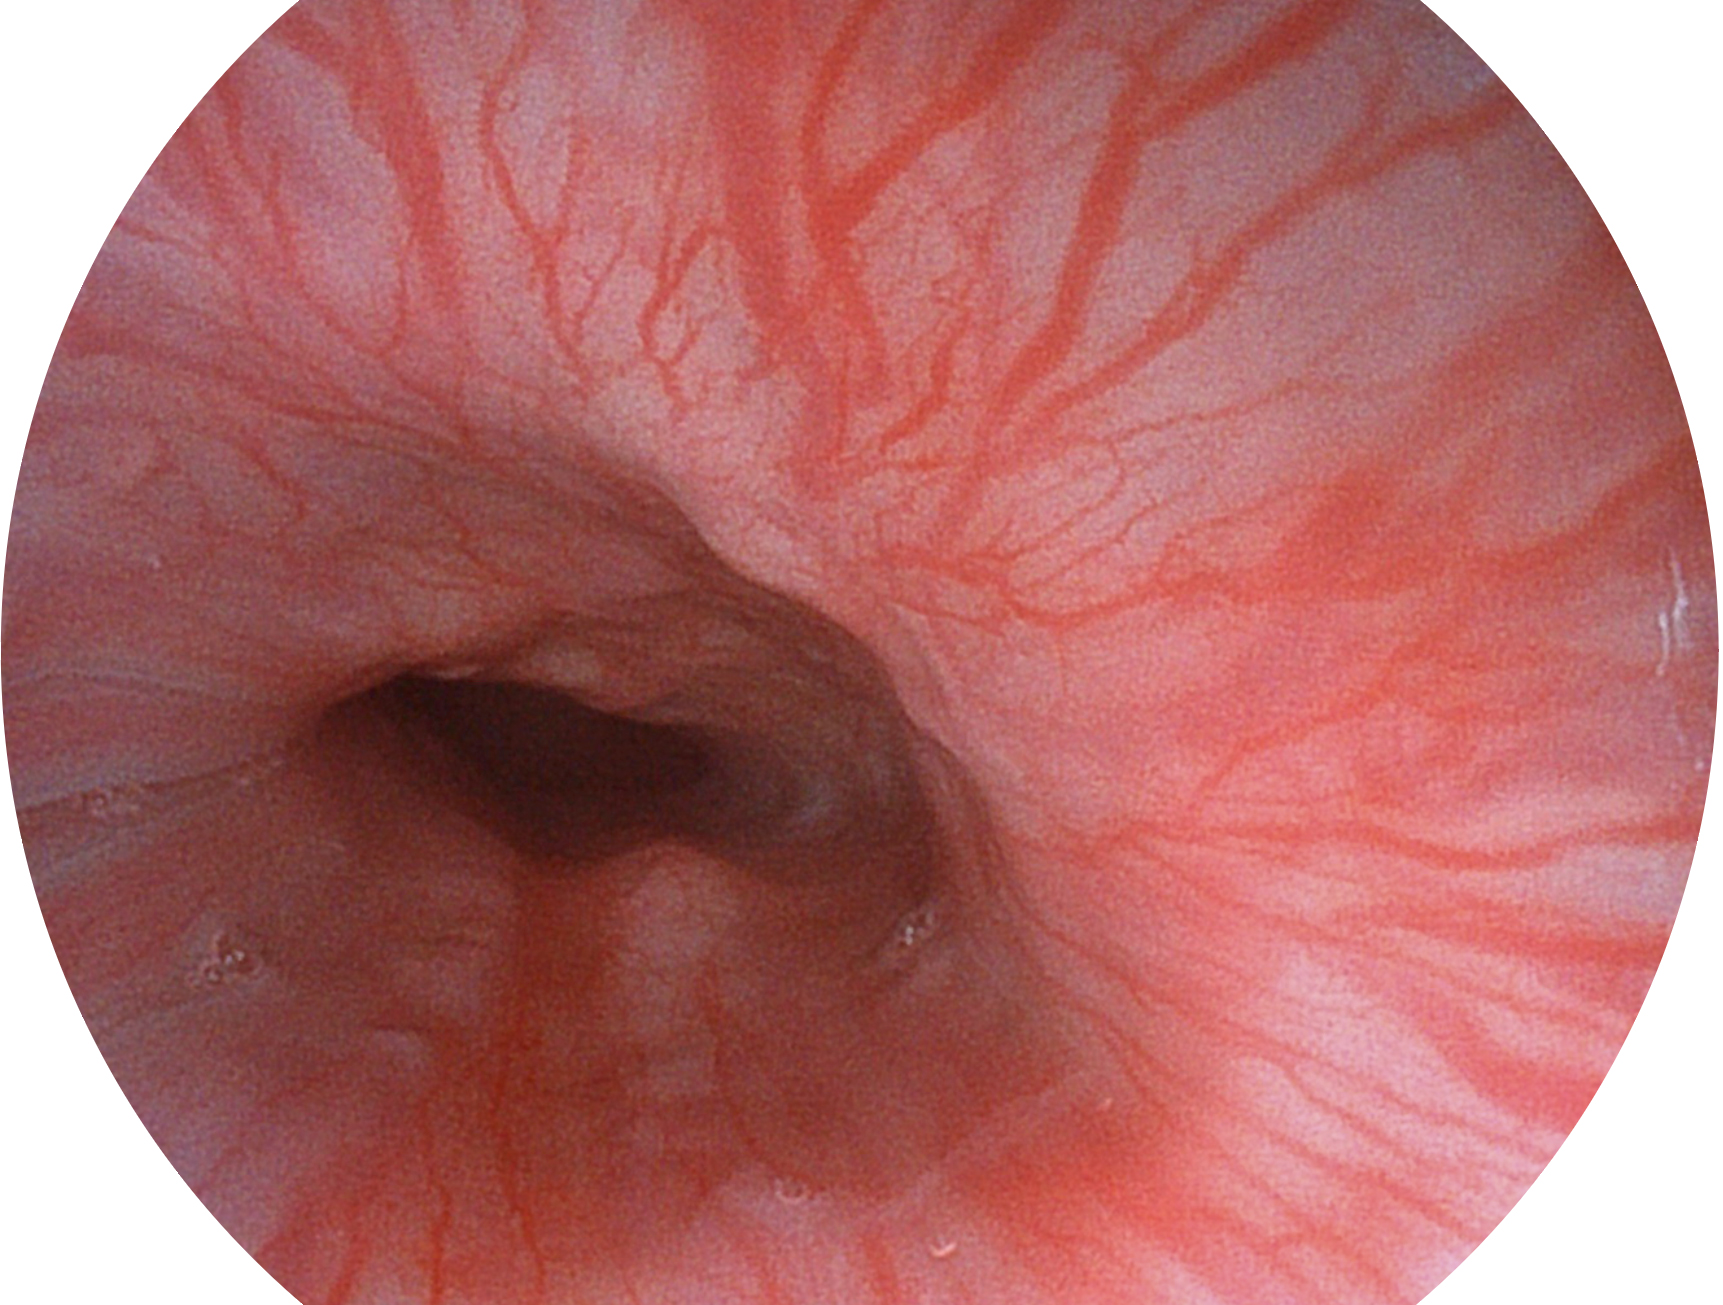

db真人体育官网新开发的内镜染色技术,主要是基于多波长LED 光源的开发,VLS-55Q 四波长LED 光源是由四个不同颜色的LED光按照相应照明模式所规定的特定发光比例进行合束后形成,合束后形成的照明光的光谱由红光、绿光、蓝光及蓝紫光这四个不同的波段范围构成。具有更高光谱自由度,通过光谱比例的控制,实现了聚谱成像技术,英文全称为“Spectral Focused Imaging, SFI”,缩写为“SFI”和光电复合染色成像技术,英文全称为“Versatile Intelligent Staining Technology, VIST”,缩写为“VIST”。